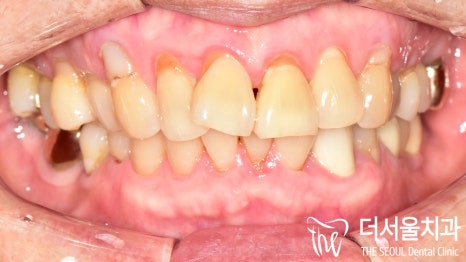

【 초진 】

이분의 경우 이가 아프다며

전체적인 검진을 받으러 오신 분입니다.

초진 구강 사진을 보면

곳곳에 생긴 우식과 치경부 마모증이

나타나 있는 것을 볼 수 있는데요.

눈에 잘 띄지 않는 곳까지 꼼꼼하게

살펴보는 것이 중요하기 때문에

치근단 방사선을 촬영하여 살펴본 결과

노인에게서 잘 발생하는 치근우식이

나타나 있는 것으로 확인되었습니다.